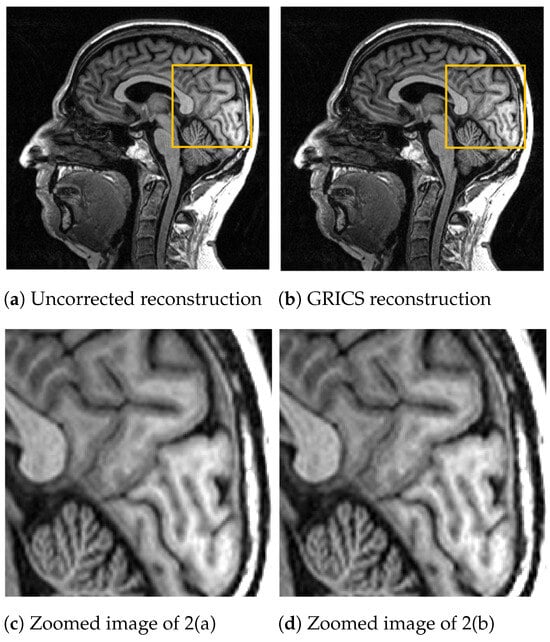

For the generalized reconstruction problem, we set . For the model optimization, we choose . The coil sensitivity maps are computed from the central lines of k-space data with 24 calibration lines and smoothed with second-order splines with a smoothing factor for both magnitude and phase. Examples of GRICS reconstruction are presented in Figure 1 and Figure 2. Figure 1 illustrates a non-rigid motion-compensated breast MRI reconstruction, where we can see an improvement in the reconstruction quality compared to the uncorrected reconstruction. Figure 2 demonstrates a rigid motion-compensated brain MRI reconstruction. The patient was instructed not to move; hence, there was no significant difference between the uncorrected and motion-corrected images. The overall maximum amplitude of motion was: 1.55 degrees for rotation and 0.7 mm for translation, indicating that the motion was minimal.

Comparison between a reconstruction without motion correction and the GRICS reconstruction. GRICS minimizes the motion artifact, dataset .

Figure 2.

Comparison between a reconstruction without motion correction and GRICS reconstruction. Sixteen motion states were considered, dataset . This MRI acquisition was conducted without obvious motion. For quantitative comparison, we determined the sharpness index [] of the images. The index was equal to for the uncorrected reconstruction and for the corrected reconstruction.